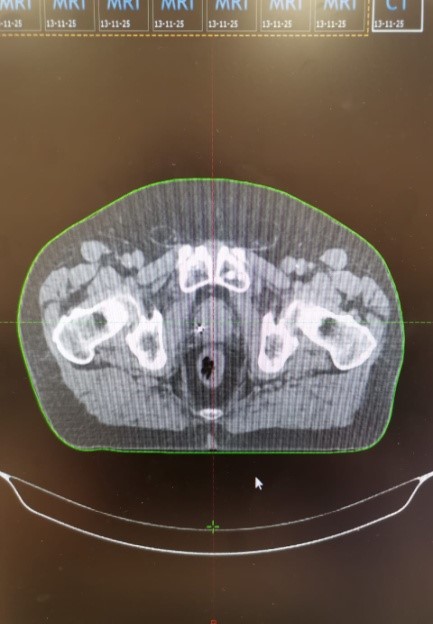

КТ-топометрия